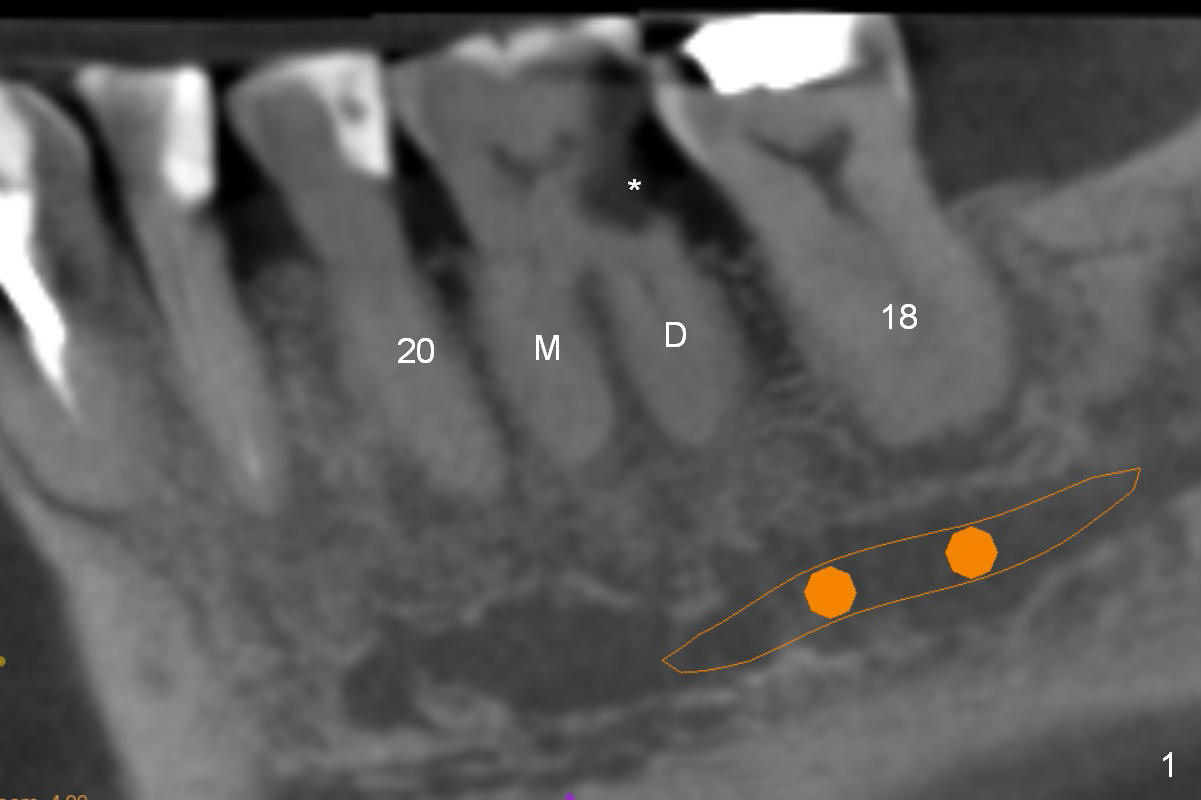

A 71-year-old man (CK) has pain in mastication when the upper left implant treatment is finished. The tooth #19 with distal caries (Fig.1 (CT sagittal section) *) seems to be non-salvageable. The mesial (M) and distal (D) roots appear to be large and closer to the root of the tooth #20 than that of #18. A large implant (7x12 mm) placed in the middle of the socket may increase the chance to invade the root of #20 (Fig.2, 4 (axial section)), as compared to that placed more distal (Fig.3,5).